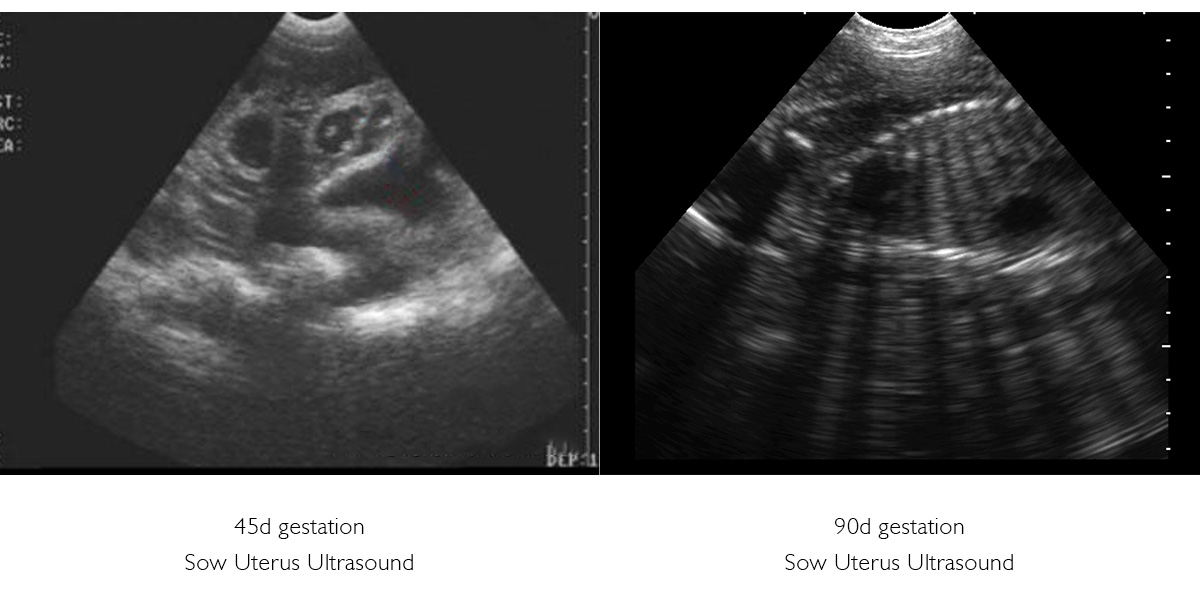

In the middle of gestation (days 30–90), veterinary ultrasound examinations can be performed to determine the number, size and viability of the foetal and to assess the uterine environment:

- Accurate estimation of the number of fetuses as a basis for subsequent nutrition and delivery

- Enables early detection of abnormalities such as foetal death or polyhydramnios, allowing early intervention to reduce miscarriages and stillbirths.